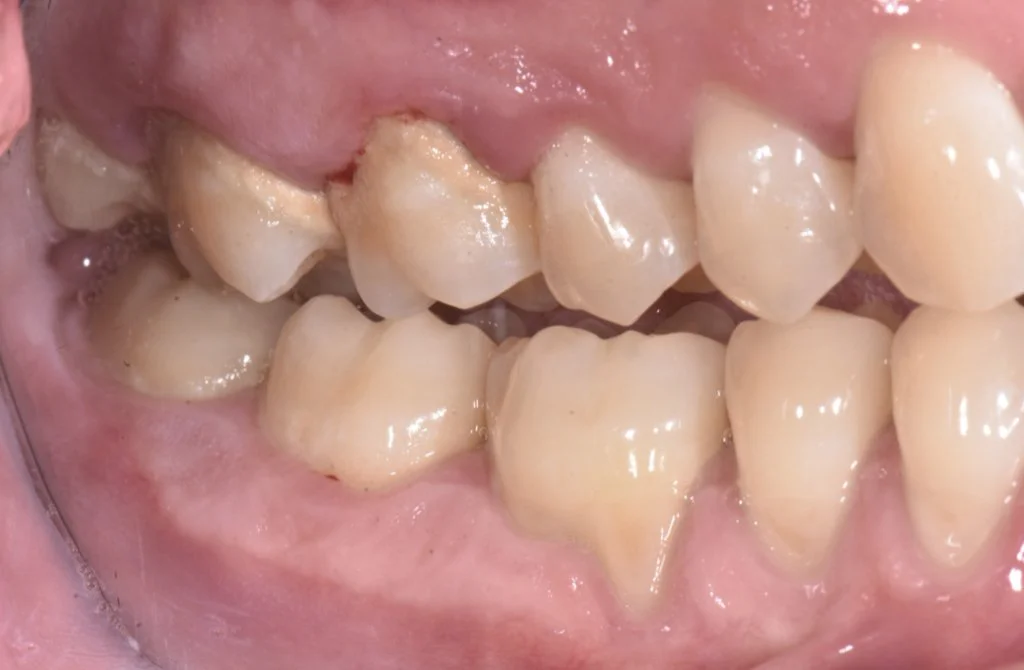

Alain a consulté suite à l’apparition de douleurs et d’abcès avec des dents qui bougent. Sa gencive est douloureuse et il a du mal à brosser. Ses problèmes sont aggravés par une maposition sévère des dents. Celle-ci ne peut être corrigée que par une chirurgie maxillo-faciale sous anesthésie général s’il le désir.

Dans son cas, un traitement parodontal non chirurgical a permis la guérison des abcès. Grace à la qualité de son brossage au quotidien, l’inflammation est résolue dans la quasi totalité des sites lésés. Alain devra suivre un programme de maintenance parodontale pour éviter une récidive de sa maladie

Cicatrisation à 3 mois